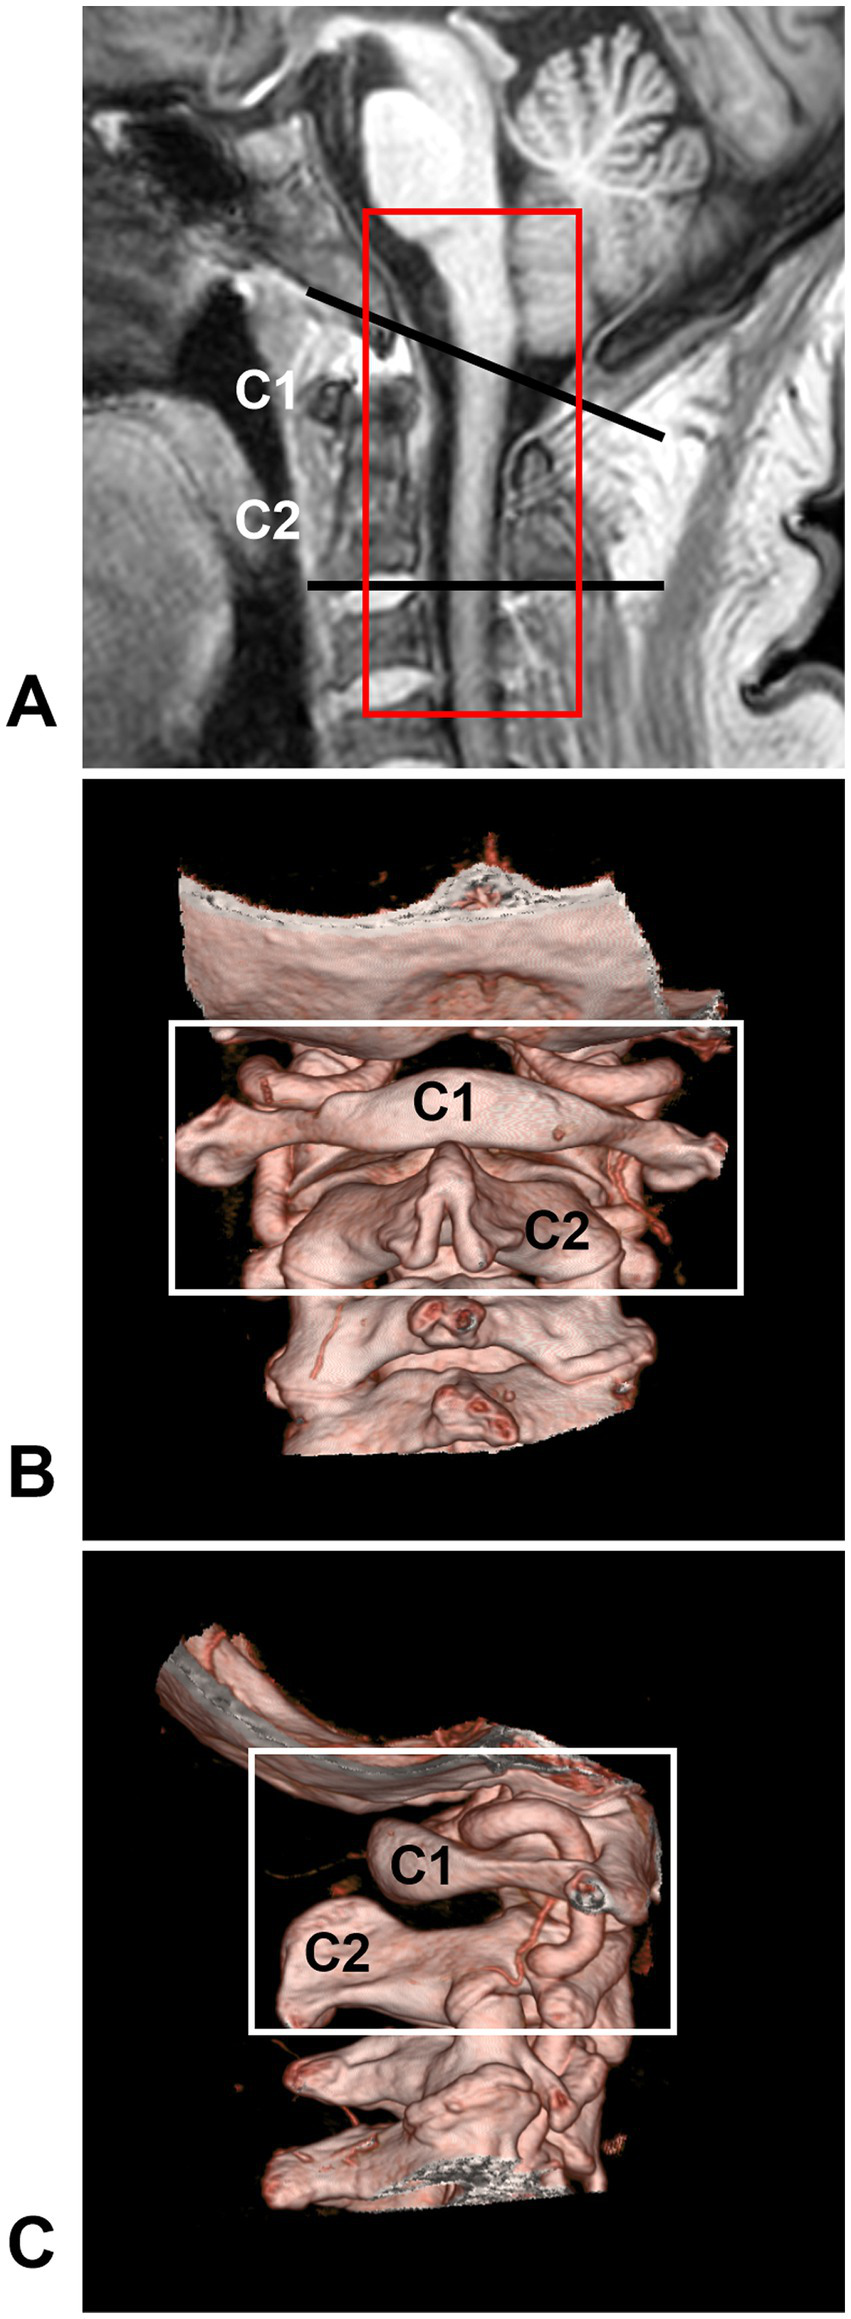

The CCJ region is located between the skull base and the upper cervical spine and is formed by the occipital bone and the first two cervical vertebrae (C1 or atlas and C2 or axis), which span both the lower brainstem and upper cervical cord (Figure 1) (2, 11, 12). The junction of the lower brainstem and upper cervical cord is situated at the level of the most rostral rootlets of the C1 nerve (13, 14). AVFs that occur in the CCJ region are called CCJ AVFs.

Figure 1

CCJ region definition. (A) MRI showing that the CCJ region was located between two black lines and formed by the occipital bone and C1-2 vertebrae. The red frame indicates the area often involved in CCJ AVF. (B,C) CTA showing the bony CCJ region (frames). AVF, arteriovenous fistula; C1-2, first and second cervical vertebrae; CCJ, craniocervical junction; CTA, computed tomography angiography; MRI, magnetic resonance imaging.